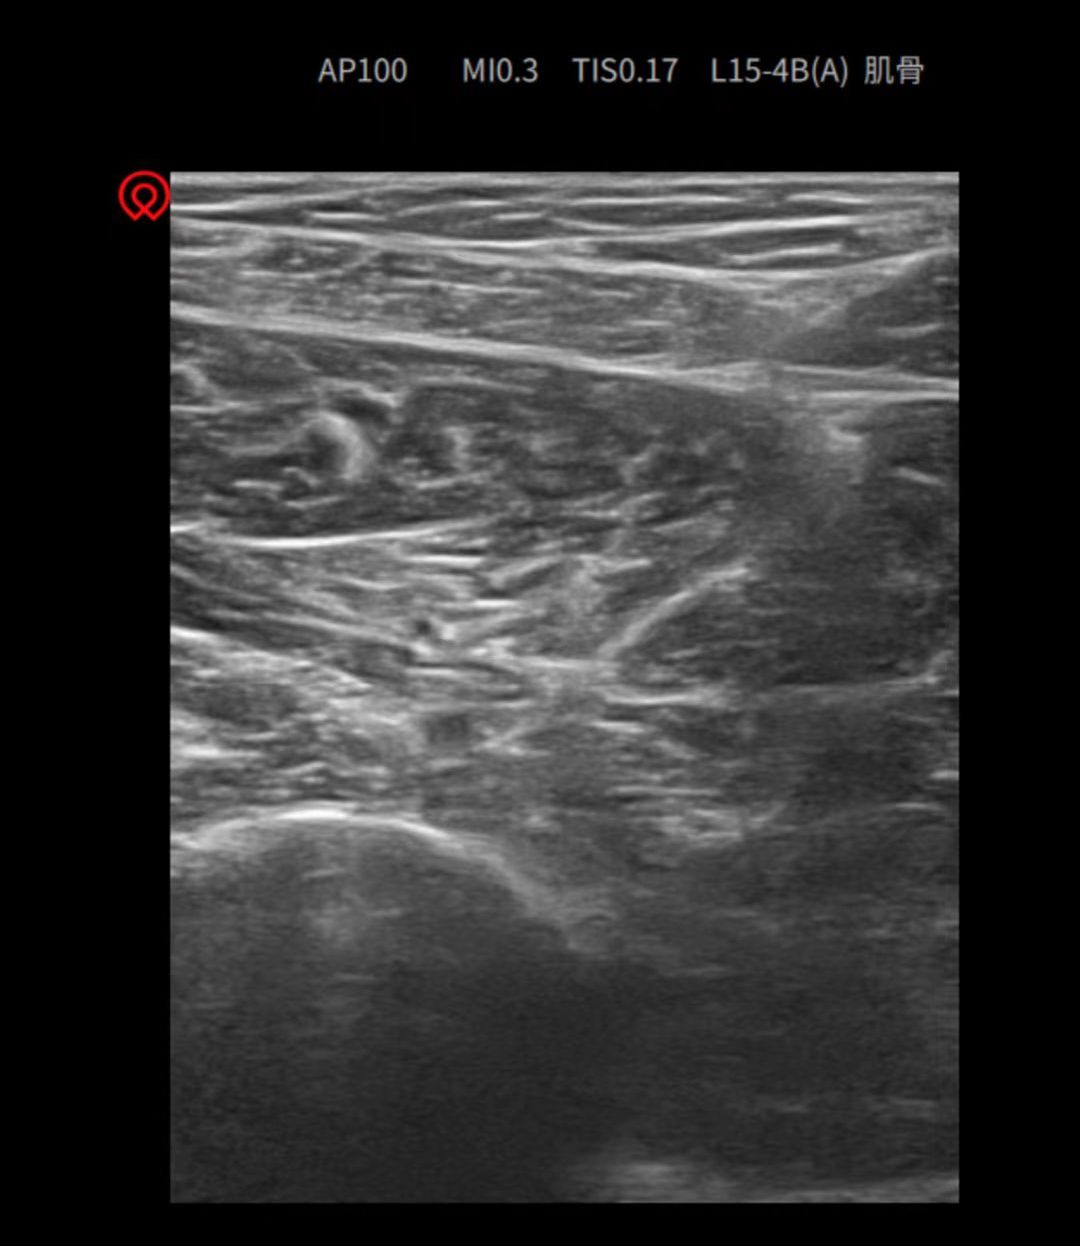

听说交大二院中医科吴仲恒副主任是神经生理学博士,在慢性疼痛性疾病治疗方面有绝招,我抱着试试看的心态住进交大二院中医科病房。吴仲恒副主任和段莹莹医师详细询问我的病史并结合相关检查,确诊我患的是“重度不宁腿综合征伴继发性睡眠障碍”。随即与中医科吴喜利主任、安鹏副主任团队联合,制定中西医协同诊疗方案。由吴仲恒副主任与段莹莹医师首先在B超引导下行神经阻滞,之后又结合吴喜利主任的中医辨证方案,给我口服中药汤剂,应用“孔圣安然枕”改善我的睡眠,配合针灸、雷火灸、中医定向透药疗法、中药足浴法等活血化瘀、通络止痛。治疗的当天晚上,我就感觉特别轻松,半夜醒了一次,没有感觉到腿疼,很快又睡着了,第二天、第三天晚上都是一觉睡到自然醒,感觉自己这么多年都没有睡得这么舒坦、安稳过。“不宁腿”就这么悄无声息的与我告别,困扰我多年的疼痛就此别过,我心情大好!听说交大二院中医科目前还在选派医生外出广州学习超声引导下肉毒素注射、神经阻滞、射频治疗、小针刀等新技术,中西医协同康复诊疗,真的是慢性疼痛性疾病患者的福音啊!